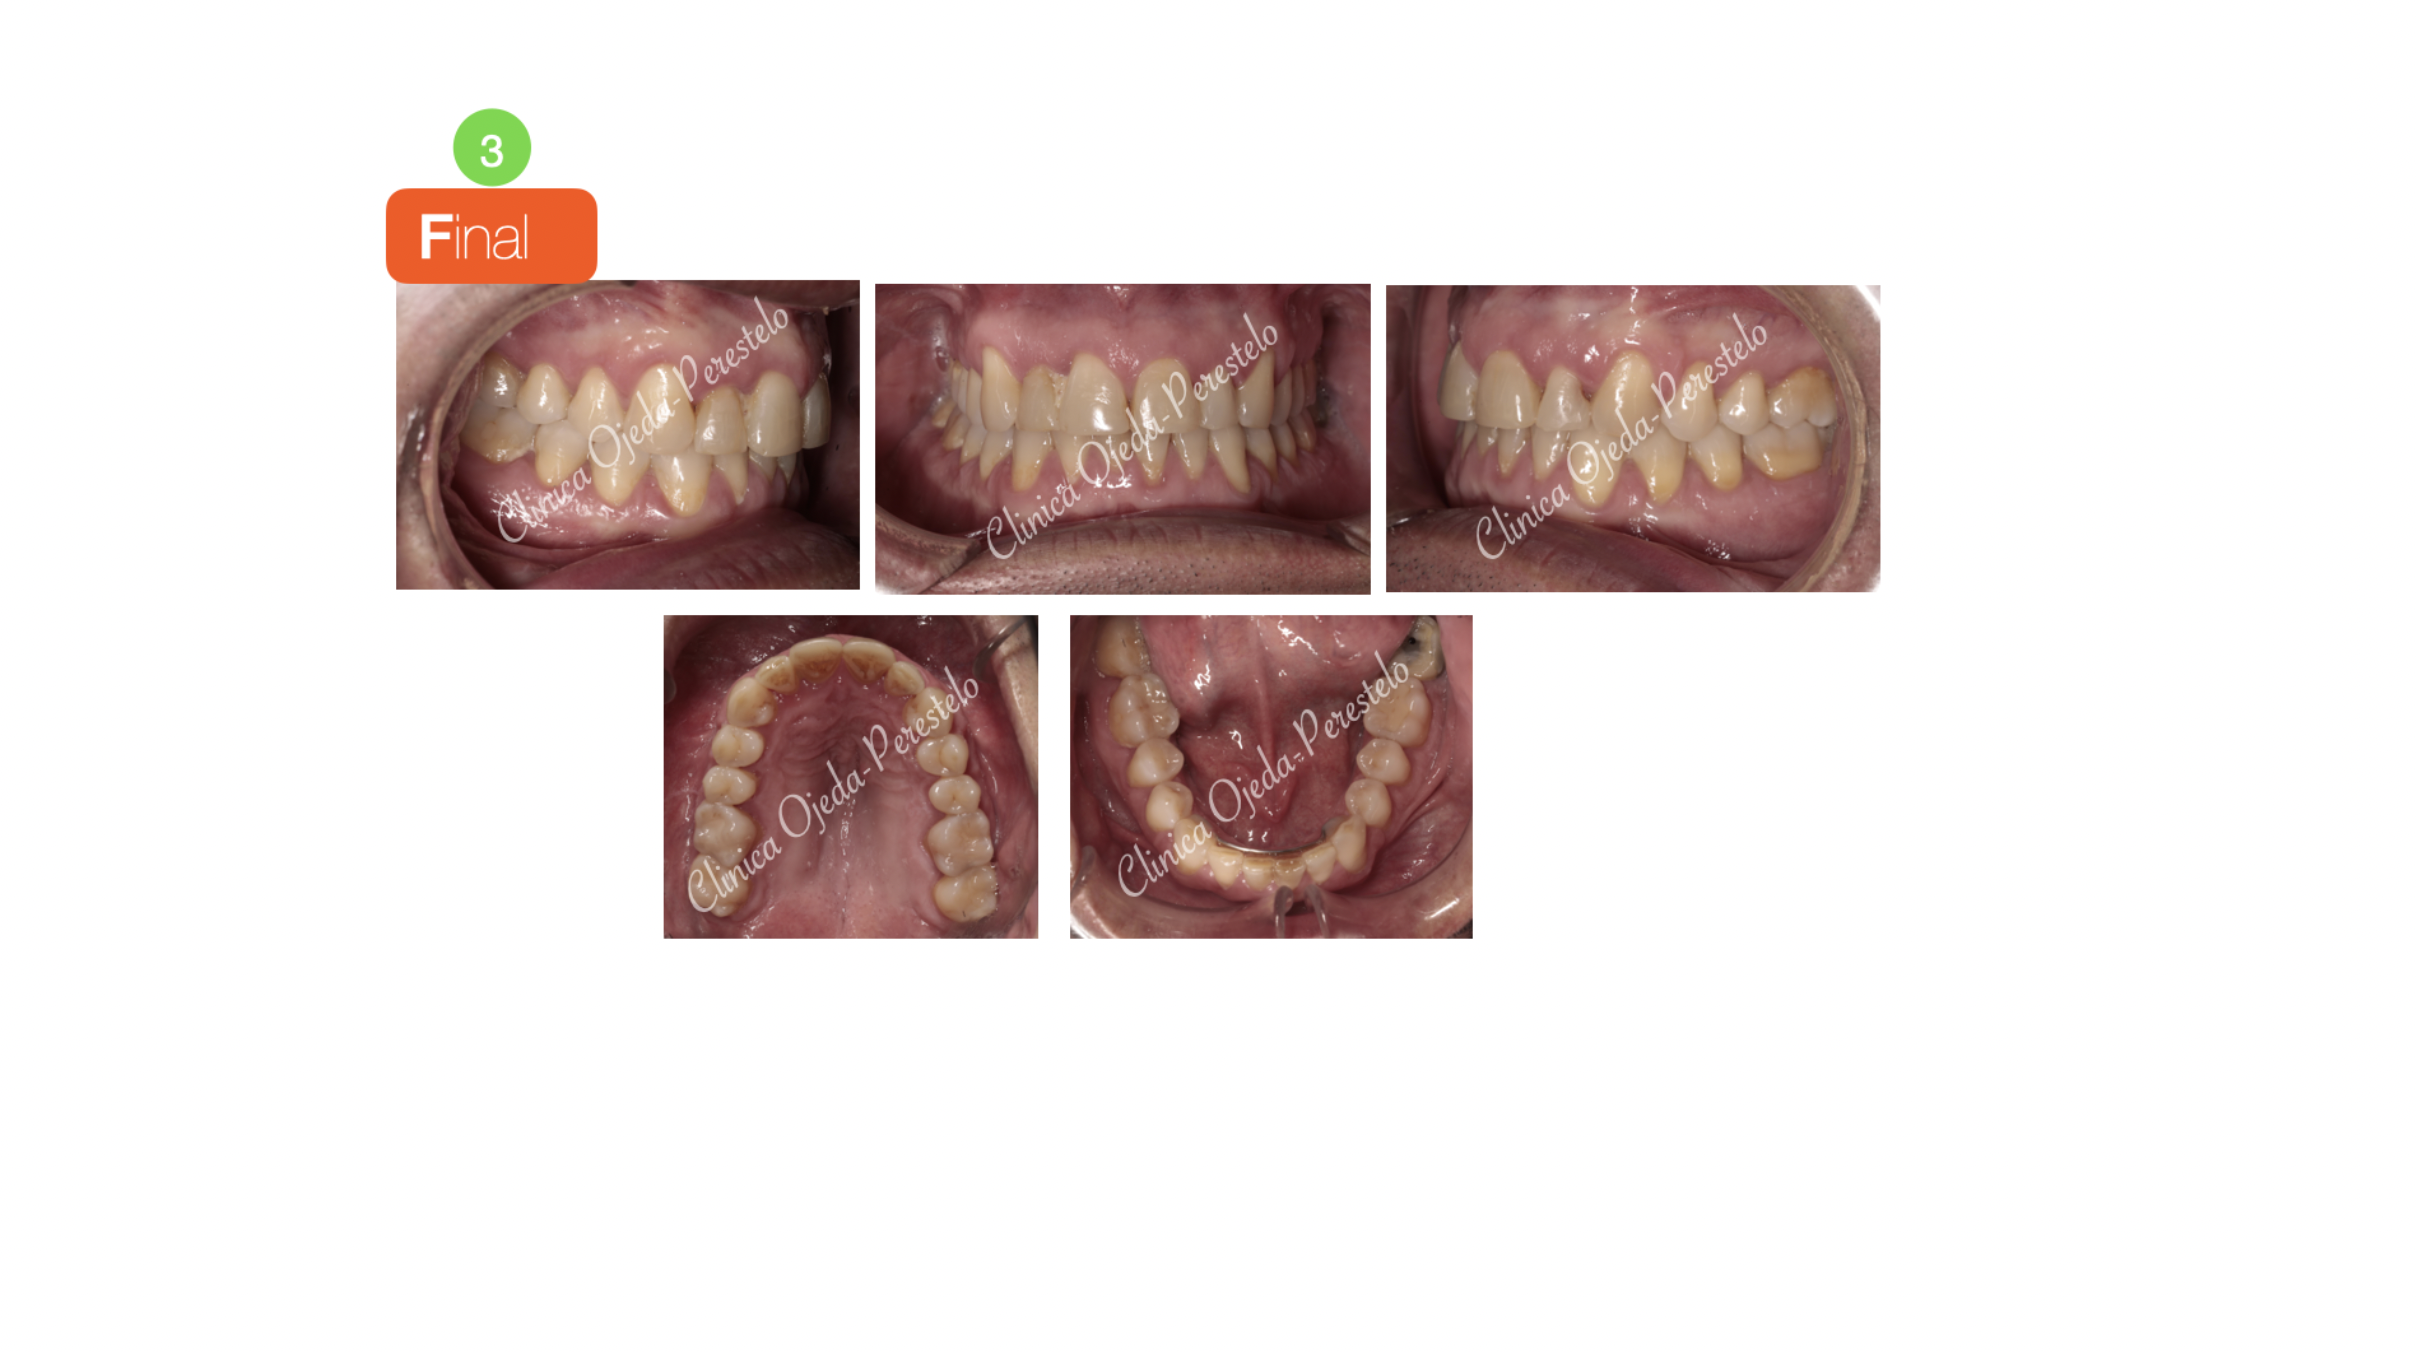

Mordida Cruzada Unilateral con Apiñamiento Severo

Los alineadores transparentes nos permiten corregir casos complejos como en este paciente con mordida cruzada y con un incisivo lateral muy palatinizado.

Queremos destacar la mejora en la amplitud de la sonrisa con un correcto engranaje dentario y centrado de las lineas medias. Todo ello se ha realizado con 147 alineadores superiores y 113 inferiores a cambio semanal combinandolo con elásticos intermaxilares. La pieza 12 presenta un pequeño remodelado del margen gingival (gingivectomia).